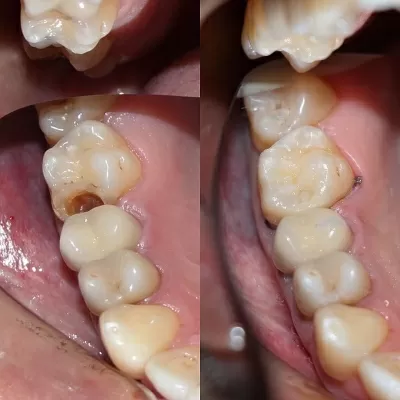

Хочу поблагодарить коллектив стоматологической клиники маэстро!!!Доктора Бардакова Игоря Викторовича и его замечательную команду, за высокий профессионализм чуткость и понимание к своим клиентам!!! Спасибо большое мои дорогие!!! Рекомендую всем кому не безразлична своя улыбка!! Приходите смело в клинику МАЭСТРО не ошибётесь!!!С Уважением Шахова раиса павловна

В стоматологическую клинику МАЭСТРО я пришла по рекомендации.Встретили меня очень тепло.ДОКТОР Игорь Викторович профессионал и умница. Зубы мои стали красивые, а я счастливая.Коллектив у Игоря Викторовича достойный.Как семья.Так приятно.СПАСИБО всему коллективу! Здоровья вам счастья,удачи,мира! Рекомендую всем, кому не все равно как выглядит ваша улыбка и здоровье ваших зубов читать далее